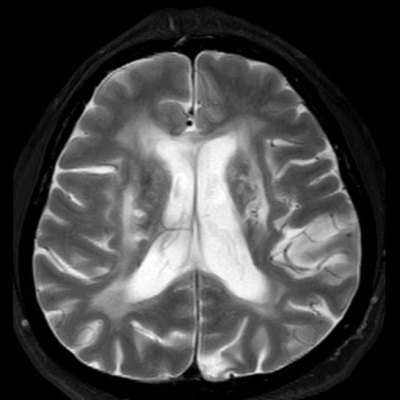

45 yaş, K

4 yıl önce akut sağ hemiparezi, konuşma bozukluğu ve dış merkezde serebellar iskemi tanısı ile ASA kullanımı öyküsü

Konuşma bozukluğu, yersiz gülme ve ağlama atakları, denge kaybı ve uyuşmaları devam ediyor

CADASIL